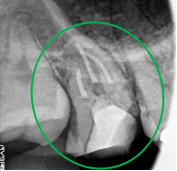

右下のブリッジの奥の方の歯が、噛むと痛い。

治療内容

被せ物の中で大きな虫歯になっていました。被せ物を取り除き、神経をとる治療をしました。メタルフリーの治療を希望されましたので、オールセラミックのブリッジを装着しました。

所感

金属を使わない治療を希望されました。体全体の健康のことを考えると、徐々に口の中の金属を減らしていくことは、とても良い事だと考えます。

オールセラミック冠(失活歯)1本:¥104,500×1本=¥104,500(税込)

オールセラミック冠(生活歯)1本:¥93,500×1本=¥93,500(税込)

オールセラミックのポンティック:¥93,500(税込)

合計:¥291,500(税込)